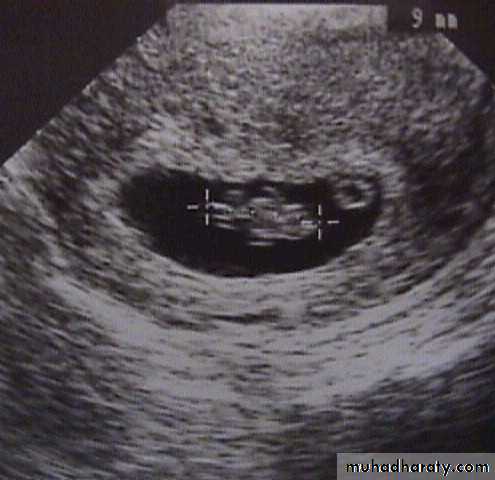

Missed abortion:

Ultrasound showed: no fetal heart and gestational sac may collapse.

If there is any doubt about diagnosis, it is wise to wait for a few days and repeat scan to see if sac is growing.